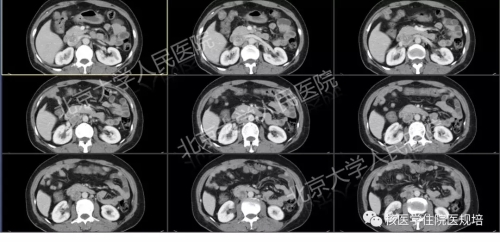

腹盆腔增强CT提示:右侧附件区囊实性占位,右心室、下腔静脉及右侧髂总静脉、右侧卵巢静脉内占位(图3-5)。

3.右心室内占位

4.下腔静脉内软组织密度影

5.右侧附件区囊实性占位,增强扫描实性部分明显强化,部分边缘与子宫分界不清。